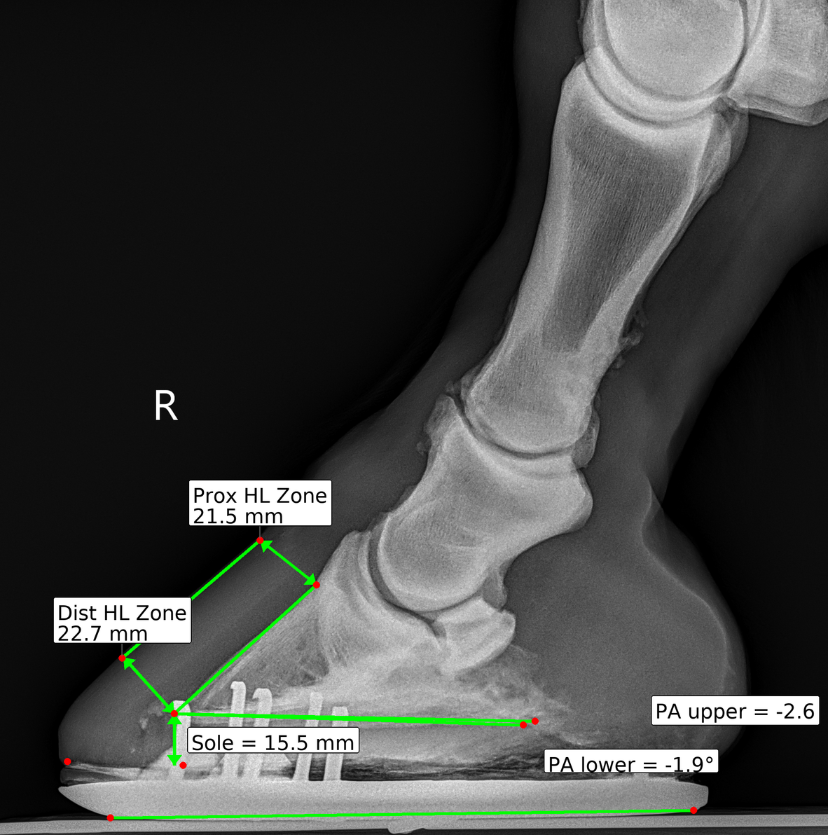

Hoof radiographs only help when both the veterinarian and the farrier can clearly see and discuss the findings. DigiHoof presents measurements and overlays in a format farriers understand and trust — improving collaboration for the horse's benefit.

Consistent overlays and measurements across visits make real comparison possible. Track hoof balance changes, sole depth progression, and alignment over time with standardized reports that speak the same language every visit.

Machine learning helps normalize landmark placement and measurements while preserving the veterinarian's clinical judgment.